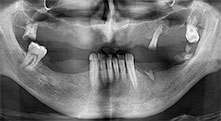

For what indications do you use the saws?

Bratu: We routinely use the instruments for harvesting bone blocks and splitting alveolar ridges. We also use the Piezomed B6/B7 for osteotomy of impacted teeth and removing failed implants. All indications that require deep, clean cuts.

Bratu: We like to use the sandwich technique for augmentation in the lateral mandible. A bone cover is prepared with the piezo saw and the crestal fragment is fixed with microscrews. We place a mixture of autologous bone and xenogenic bone replacement material in between. This works very reliably. You should always ensure sufficiently dimensioned vertical cuts when splitting the alveolar ridge in the mandible. Otherwise the bone may fracture easily.